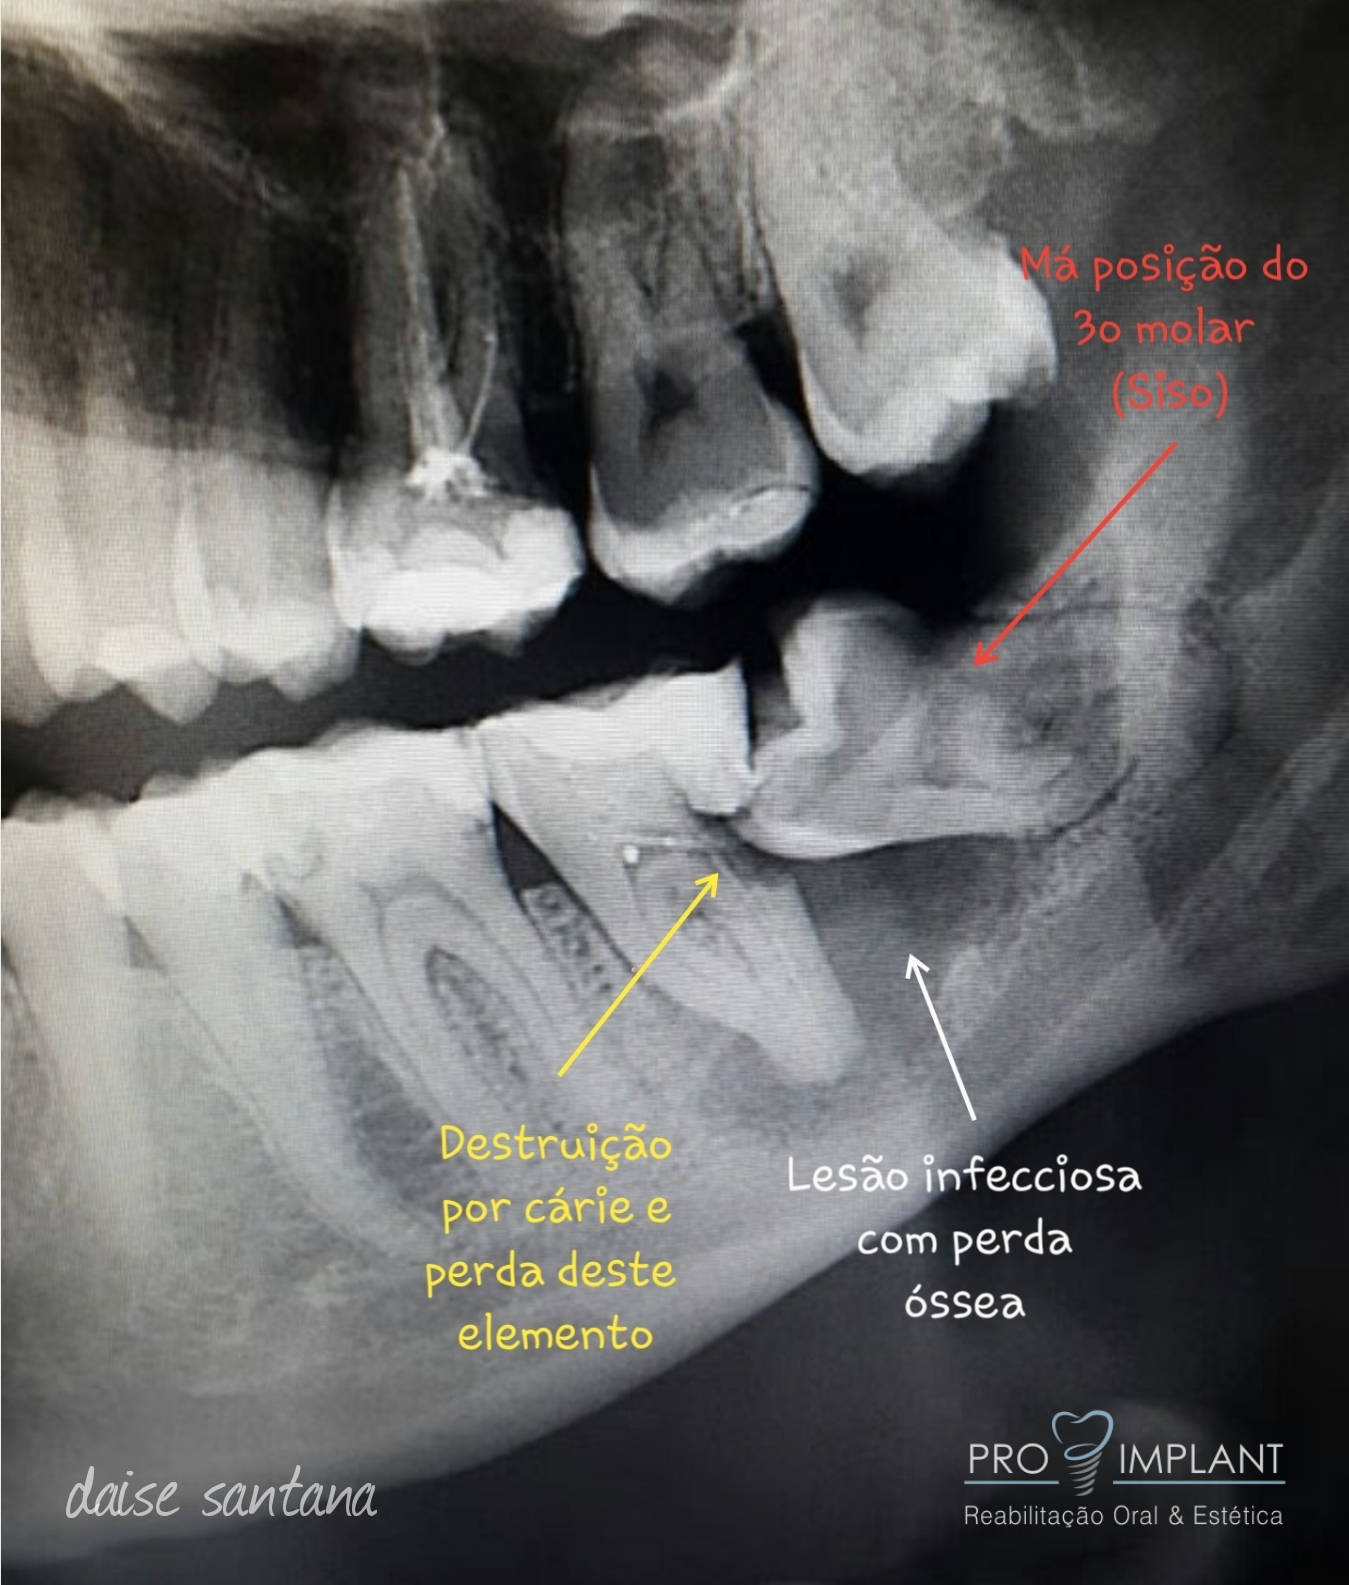

Dentre estes procedimentos podemos destacar: exodontia de terceiros molares (dentes do siso), cirurgias para remoção de pequenas lesões, cirurgias pré-protéticas, entre outras. As Cirurgias Orais são muitas vezes a solução para um bom resultado.